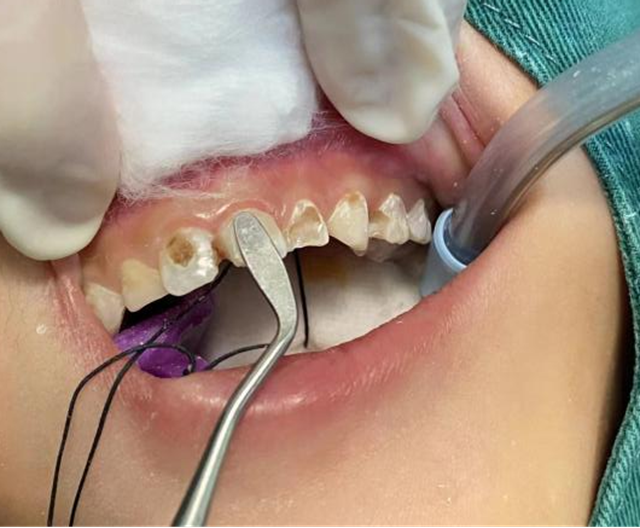

西南医大中医院口腔诊疗中心黄丹医生正要给5岁的豪豪(化名)检查坏掉的牙齿,结果还没等靠过去,豪豪就嗷地一声开始打滚式逃避,一边的妈妈怎么都按不住,安抚了半天,汗水都整出来了,豪豪就是不配合。

“全麻口腔治疗吧,小家伙的牙齿得赶紧处理了。”黄丹医生确认豪豪没有手术禁忌症后,为豪豪完善了相关检查,制定了全麻下舒适化儿童口腔治疗方案。

到了手术时间,麻醉科医生为豪豪实施了全身麻醉,黄丹很顺利地为豪豪完成了治疗。手术结束后,豪豪就复苏了,黄丹给家长交代了注意事项后,他们就回家了。